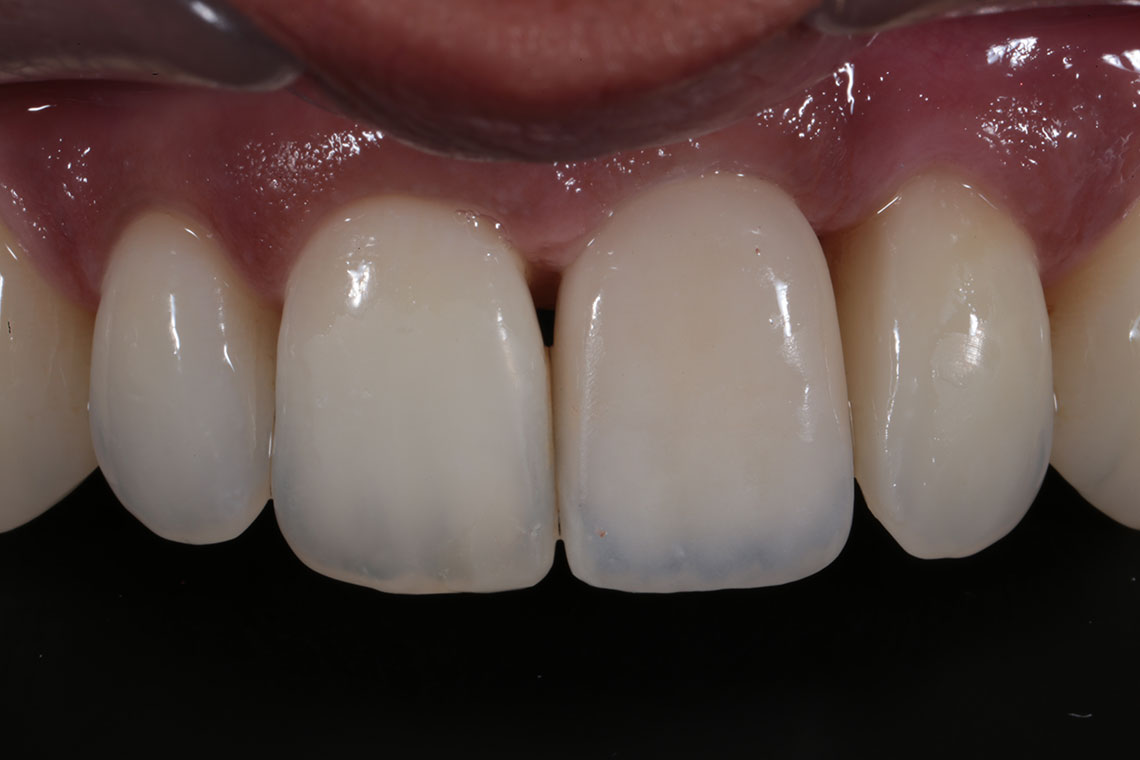

This lovely lady attended with very low confidence due to her teeth and smile. Gum disease and trauma had led to the teeth drifting. One of her front teeth was so loose that it needed to be replaced. We started by providing intensive treatment with our dental hygienist to treat the gum disease. Following this Invisalign® braces were used to align the teeth and the teeth were whitened. A dental implant was then placed to replace the loose front tooth and composite bonding was performed to the adjacent front tooth. The change in the patient’s confidence as a result of this work was breathtaking.

I have been extremely pleased with the treatments I have had here - Invisalign, composite bonding and whitening. My teeth look a million times better and the staff have been nothing but warm, friendly and professional.